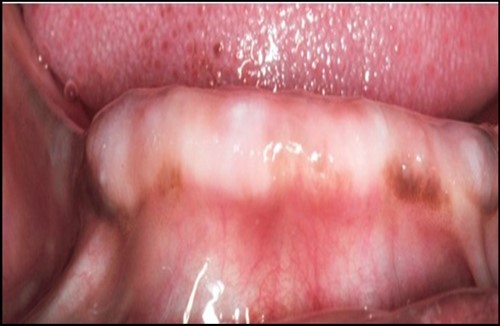

Post operatively after 3 months, osseointegration was evaluated clinically and radiographically (Figure 5a,b) and the implants were well prepared to receive the prosthesis. The second stage surgery was performed in which cover screws were removed and healing abutment were inserted into the implants (Figure 6). After a time period of two weeks, peri-implant soft tissue healing was examined, and existing denture was relined after relieving at the abutment site. Later, the healing abutment is removed using a 1.25 mm hex driver. Internal portion of the implant is irrigated and dried to make sure if it is free of debris and soft tissue. A periodontal probe was used to measure the gingival cuff height at the right and left canine site of implant location. Selected ball abutment were placed onto each implant using 1.25 mm hex driver and 30 Ncm torque wrench (Figure 7A).